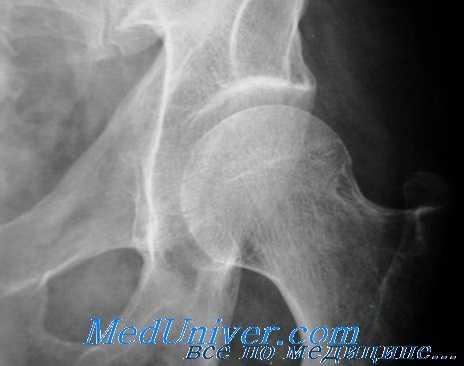

- 2 стадия (импрессионных переломов). На рентгенограмме выявляется гомогенное затемнение, отсутствие структурного рисунка в зоне поражения, локальные уплотнения и снижение высоты головки, расширение суставной щели. Обнаруживается большое количество микропереломов.

- 3 стадия (секвестрации). Головка становится еще более плоской, теряет нормальные контуры, суставная щель продолжает расширяться. На снимках визуализируются отдельные фрагменты кости различного размера и формы, не имеющие нормальной структуры. Определяется утолщение и укорочение шейки бедра.

- 4 стадия (репарации). Фрагментированность костного вещества исчезает. Головка бедренной кости нормально контурируется, однако ее структура еще не восстановлена. В костном веществе иногда просматриваются кистовидные очаги просветления.

- 5 стадия (деформирующего артроза). Костная структура восстанавливается, сохраняется деформация головки, возникшая на 2 и 3 стадии. Головка плоская, расширенная, не совпадает по форме с суставной впадиной. На ее поверхности видны остеофиты, в кости выявляются кистозные полости, образовавшиеся на фоне дистрофических процессов.

- Рентгенография тазобедренного сустава. Для повышения информативности используются специальные укладки по Лаунштейну. Вначале на снимках просматриваются участки со сниженной плотностью под субхондральной костью, придающие поверхностным частям головки вид «яичной скорлупы». Затем становится видна деформация головки и некротический очаг в виде плотной тени, окруженной более светлым ободком. В исходе визуализируются изменения, характерные для деформирующего артроза.